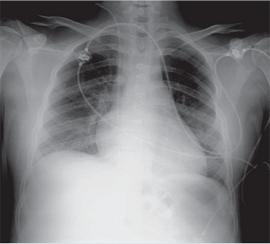

El paciente tuvo una mejoría respiratoria progresiva que permitió extubación programada 48 horas después. El angioTAC de control mostró leve disminución de tamaño del hematoma retroperitoneal derecho sin signos de sangrado activo; un patrón pulmonar con afectación de ambas bases y língula de posible origen inflamatorio. En la radiografía de tórax, realizada al cuarto día de hospitalización, desaparecieron las lesiones previas (Figura 3). No requirió nuevas transfusiones de productos sanguíneos y mantuvo buena dinámica respiratoria sin necesitar oxígeno suplementario.